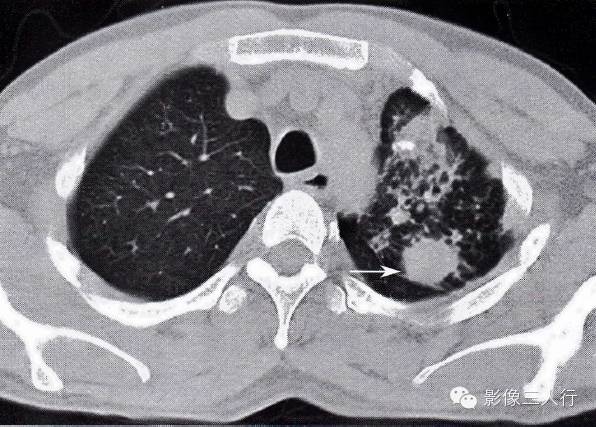

图2-93肺癌在肺结核病灶内

患者痰查结核杆菌阳性,左肺下叶斑片状影,密度较淡,边缘模糊,其内有包块影,大于3cm,有分叶,与胸膜紧贴,肺穿刺为肺鳞癌